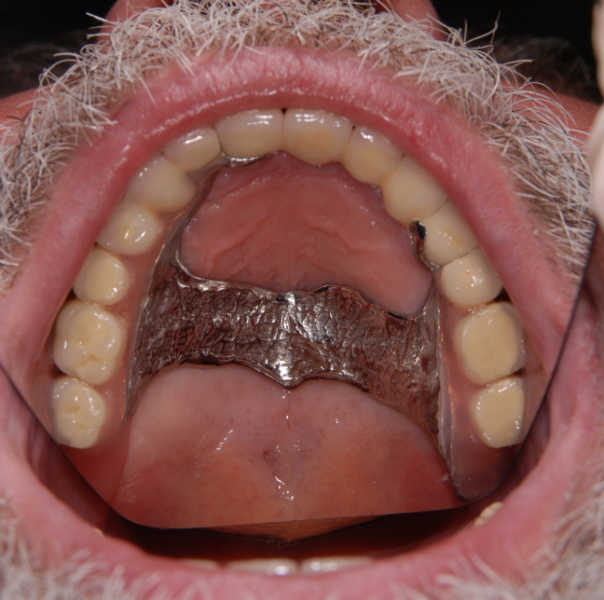

Intra oral view before treatment

Intra oral view after treatment